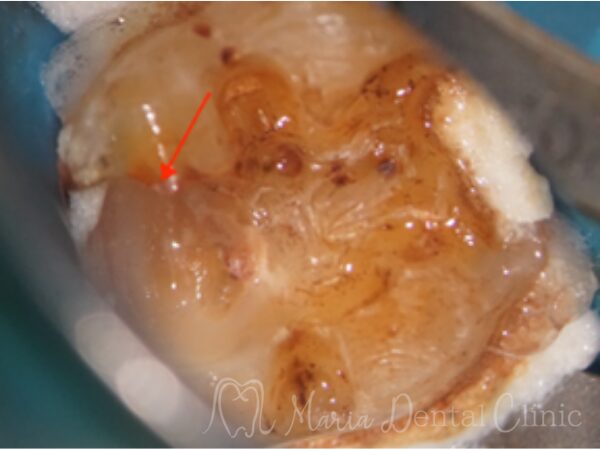

赤矢印は2次虫歯部位を指す

マイクロスコープで治療を開始した際に同部位を確認すると、歯科充填材料の下に広がる虫歯を確認し、通法通りのコンセプトに基づき精密根管治療を施しました。